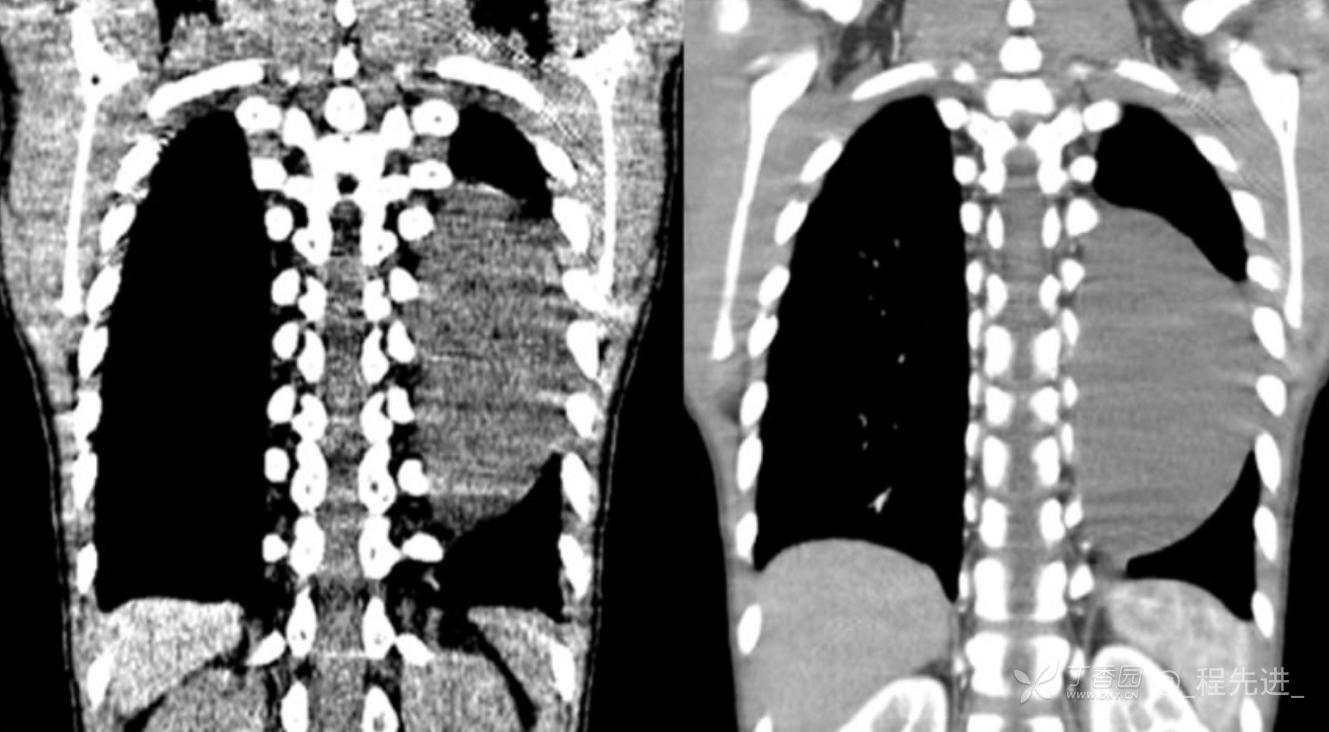

11月特别精彩病例|胸片示“左侧胸腔包裹性积液”,CT增强你诊断啥?【病理已公布】

呱呱叫了 等 3 位达人已点赞男,11岁,患儿因其爷爷近期在我院诊断“肺结核”,于外院行结核筛查,胸片示“左侧胸腔包裹性积液”,近期无咳嗽、发热、纳差、盗汗、乏力、胸痛、胸闷、气促不适,精神反应可,为求明确“左侧胸腔包裹性积液”病因,遂来我院门诊就诊,门诊以“胸腔积液查因”收住入院。发病以来,精神尚可食欲如常,大便如常,小便量如常,体重无明显变化